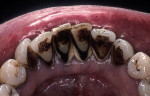

When fiber-reinforcing materials were introduced, the focus for their use was for periodontal splinting and stabilization resulting from tooth mobility.6,10,16,41-43 There is no doubt that splinting does reduce tooth mobility while the splint is in place.44 In the last decade, research supports the use of periodontal splinting as recommended therapy to stabilize those teeth to improve long-term prognosis.45-47 In a long-term clinical evaluation of splinting over a period of 48 to 96 months, using the original Ribbond Reinforcement Ribbon in fiber-reinforced composite resins was highly successful.17 The success of these splints can be attributed to close adaptation of the fiber ribbon to the tooth surface combined with cross stabilization of the mobile teeth by placing adhesive composite resin on the facial surfaces (Figure 4A, Figure 4B, Figure 4C, Figure 4D, Figure 4E).34,35 Splinting of traumatized teeth with fiber-reinforcing materials and adhesive composite resin has also been reported.48,49 When using fiber to stabilize the traumatized tooth or teeth or for tooth stabilization after re-implantation, the tooth must be allowed to have some movement and not be fixed in place.50,51